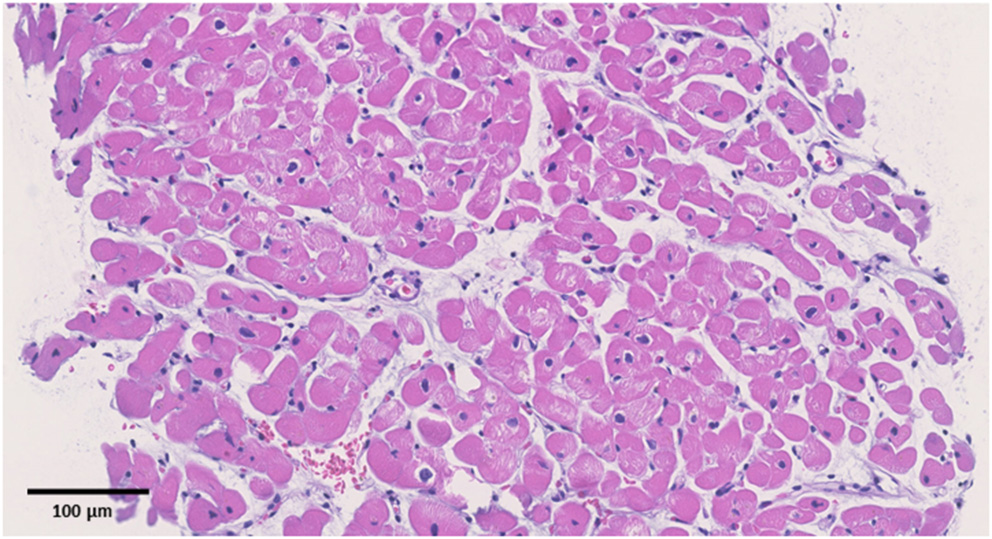

Figure 2

Pathological specimens. Hematoxylin and eosin staining (original magnification Ă—200). The black bar indicates 100 ÎĽm. No apparent signs of inflammation were observed.

Upon admission to our hospital, the patient had blood pressure, heart rate, and body temperature of 135/65 mmHg, 97 bpm, and 37.3°C, respectively. Chest radiography showed no signs of cardiomegaly or pulmonary congestion. Blood tests revealed an elevation in white blood cells (9,560/μl) and C-reactive protein (4.44 mg/dl, normal range ≤0.3 mg/dl), together with elevations in cardiac enzymes, including CK (818 IU/L, normal range 62–287 IU/L), CK-MB (59 IU/L, normal range 2–21 IU/L), and cardiac troponin T (1.41 ng/ml, normal range ≤0.014 ng/ml). The N-terminal pro-brain natriuretic peptide (NT-pro BNP) level was also elevated (221.2 pg/ml, normal range ≤ 125 pg/ml). Electrocardiography revealed ST elevations in V2–V5 leads, whereas echocardiography revealed systolic dysfunction (LVEF = 55%) associated with left ventricular dilatation (LVDd, 55 mm) without any pericardial effusion. Coronary CT showed no signs of coronary atherosclerosis. A myocardial specimen obtained from the septum of the right ventricle showed no apparent signs of myocardial destruction or inflammation (Figure 2). Hemodynamic evaluation by Swan–Ganz catheterization revealed a pulmonary artery pressure of 27/11 (19) mmHg, pulmonary capillary wedge pressure of 13 mmHg, and cardiac output of 6.62 L/min. Cardiac MRI revealed diffuse late gadolinium enhancement at the epicardium (Figure 1B) that was similar but somewhat different from the images observed 3 years prior when he suffered from his previous myocarditis (Figure 1A). A T2-weighted MRI revealed diffuse high-intensity areas, suggesting edematous changes in the left ventricle during his previous bout of myocarditis, as well as during the current myocarditis (Figures 1C,D). Enzyme-linked immunosorbent assays of sera were all negative for potential causes of viral myocarditis (Coxsackie, echo, influenza A and B, cytomegalovirus, and Epstein-Barr virus (EBV)]. Negative T waves were observed in V3 to V6 leads following electrocardiography on day 5 (Supplemental Material). All the aforementioned results, except for pathological findings from the myocardial specimen, were consistent with a diagnosis of COVID-19 mRNA vaccination-related myocarditis. We ruled out acute coronary syndrome given the absence of cardiac asynergy and cardiac MRI findings. We also ruled out acute systolic heart failure of any cause based on the hemodynamic evaluation findings by Swan–Ganz catheterization.

Currently, myocarditis is being recognized as one of the complications of COVID-19 mRNA vaccination (1–3). Albeit rare, the prognosis of this condition seems to be quite good. Nonetheless, more information on risk factors for this unfavorable phenomenon needs to be collected (6–8). So far, epidemiological studies have suggested that this condition is more frequently observed among young adult and adolescent males (6–8). However, it is unclear whether a history of other types of myocarditis can be considered a risk factor. In this report, we present the first-ever documented case of myocarditis associated with COVID-19 mRNA vaccination in a patient who had a history of myocarditis (Supplemental Material). Based on a series of investigations, including cardiac enzymes, electrocardiogram, echocardiography, and cardiac MRI, we found similarities between COVID-19 mRNA vaccination-related myocarditis and myocarditis associated with Campylobacter jejuni. We observed unique yet similar patterns on cardiac MRI wherein diffuse late gadolinium enhancement was located mainly at the epicardium during both the current COVID-19 mRNA vaccination-related myocarditis and the previous myocarditis episode associated with Campylobacter jejuni. Cardiac MRI has been considered a useful modality for diagnosing acute myocarditis (10, 11) given its great potential for not only diagnosis but also understanding of the pathophysiological mechanism of COVID-19 mRNA vaccination-related myocarditis (12–14). There are several limitations to be considered. First, we obtained three specimens at the time of endomyocardial biopsy. Although the patient had no apparent signs of myocardial destruction or inflammation from the endomyocardial biopsy, a diagnosis of myocarditis was established because of his elevated cardiac troponin T, elevated creatinine kinase, reduced EF, changes in the electrocardiogram, and MRI findings. Second, we could not determine the causal association between the history of myocarditis and the current vaccination-associated myocarditis. Third, we did not compare the cardiac MR images between the previous and current myocarditis episodes. Thus, the diffuse late gadolinium enhancement at the epicardium observed during the current myocarditis episode may not have represented acute myocarditis. However, we observed edematous changes in the myocardium using T2-weighted MR images. In addition, the area of late gadolinium enhancement at the epicardium observed in the current myocarditis episode was somewhat different from that of the previous one. These facts support the notion that late gadolinium enhancement at the epicardium observed in the current episode represents acute myocarditis. Lastly, we were unable to perform the suggested immunohistochemical testing on our biopsy specimens to investigate whether there were any autoantibodies against the myocardium. The second episode might, indeed, be associated with post-infectious autoimmune syndrome; however, this situation has been described as a chronic condition rather than an acute one with complications in multiple organs (1). Of note is that the mechanism of myocarditis induced by mRNA vaccination remains unclear. In most cases without a history of previous myocarditis, molecular mimicry between the spike protein of virus and self-antigens, trigger of pre-existing dysregulated immune pathways in certain individuals, immune response to mRNA, activation of immunologic pathways, and dysregulated cytokine expression have been proposed (8). However, in this case with a history of myocarditis, there may be something more in addition to these common mechanisms, although observations from a single case cannot produce any concrete evidence.